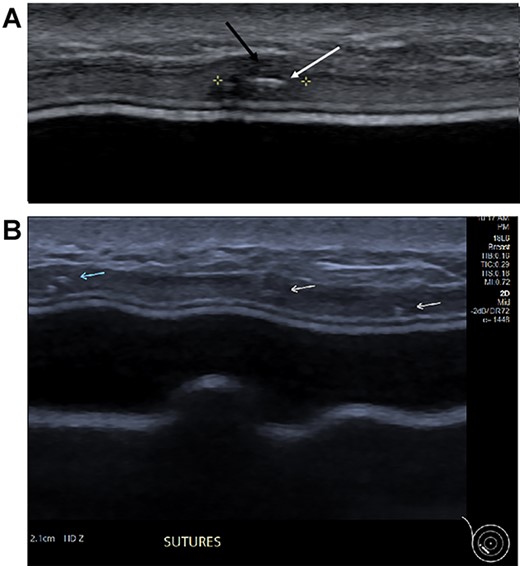

Three months postoperatively, the patient presented to the breast clinic with a nodule on the lower part of her left reconstructed breast deep to her (wide excision) scar. Ultrasound revealed an indeterminate nodule with a bright echoic centre. Differentials included the unabsorbed knot of an internal suture or possible local recurrence. Dynamic contrast breast MRI, however, did not demonstrate any abnormal enhancement. Ultrasound undertaken along with the operating surgeon demonstrated the patch of ADM inserted at the time of initial surgery as a thickening, with three identical regularly placed nodules measuring 3–5 mm corresponding to PDS sutures (Fig. 4), thus avoiding unnecessary surgery. Four months post-operatively, the nodule was no longer palpable.

(A) Magnified ultrasound image identified a 5 mm hypoechoic focus of thickening within the capsule (black arrow and area between the cursers) with two parallel lines centrally within the focus which represents the suture (white arrow). (B). The ultrasound demonstrates the equally placed sutures identified as small white parallel lines (arrows) across the ADM.